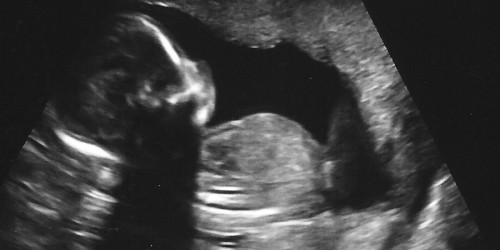

I m married on 2010 . My first baby was tubual pregancy . So they removed right tube. 2 nd and 3 rd was no heart beat. So they given tabelt and removed and 4 th was got heart beat but at 8 th week while checking in ultra sound no heart beat so they done d/c. Now i m confused shall i can conceive without fear. Next i get good child.pls help me.